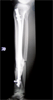

18 years old male with malunion distal tibia

Pre

Op

Xrays of limb